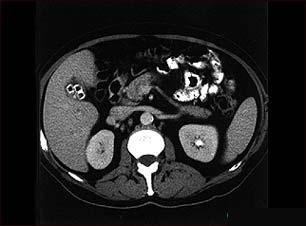

Litiaza biliara (calculii biliari)